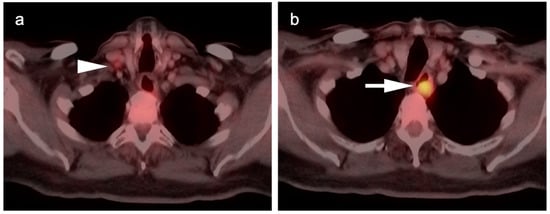

5. Cholangiocarcinoma